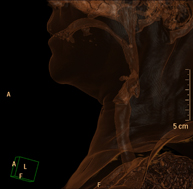

Prueba radiológica que consiste en obtener imágenes del cráneo de alta definición anatómica (tronco cerebral, cerebelo, cerebro, calota craneal, etc.), mediante el empleo de un equipo de TC (Tomografía Computarizada).Indicaciones: traumatismos, cefalea, trastornos de la memoria, pérdida de fuerza súbita en una extremidad o mitad del cuerpo. - TC Cuello

Prueba radiológica que consiste en obtener imágenes del cuello de alta definición anatómica mediante el empleo de un equipo de TC (Tomografía Computarizada). Indicaciones: estudio de tiroides, control de tumores tratados, estudio de ganglios, infecciones y abscesos. - TC Laringe

Prueba radiológica que consiste en obtener imágenes de la laringe de alta definición anatómica mediante el empleo de un equipo de TC (Tomografía Computarizada). Indicaciones: afonía súbita o crónica, dificultad respiratoria. - TC Órbitas

Prueba radiológica que consiste en obtener imágenes de las arterias carótidas del cuello de alta definición anatómica mediante el empleo de un equipo de TC (Tomografía Computarizada) y la inyección de contraste intravenoso. Posteriormente, las imágenes son reconstruidas en tres dimensiones (3D). Indicaciones: accidente vascular cerebral agudo, accidente vascular transitorio, soplo carotídeo. - TC Columna cervical

Prueba radiológica que consiste en obtener imágenes de las vertebras cervicales de alta definición anatómica mediante el empleo de un equipo de TC (Tomografía Computarizada). Indicaciones: cervicalgia sin/con irradiación a brazos, traumatismo.